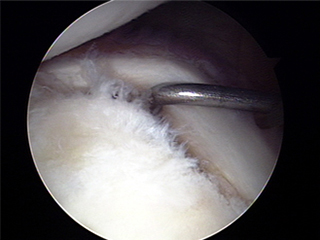

2. 수술은 관절경 수술로 대부분의 습관성 탈구가 치료 가능하다.

수술 전